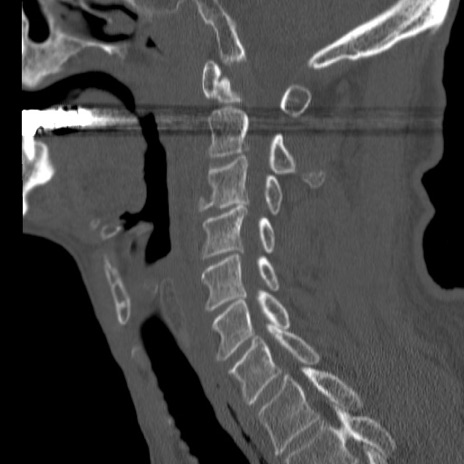

症例46 頚椎CT(矢状断像)

【症例】80歳代男性

【主訴】両側頚部〜上肢のしびれ

【現病歴】昨日、自宅内で転倒、その後より上記症状あり。意識障害なし。

【身体所見】両側上肢のallodynia(熱痛覚過敏)あり。MMTおよびDTRは正確な所見取れず。両上肢の挙上はなんとか可能。

異常所見と診断は?